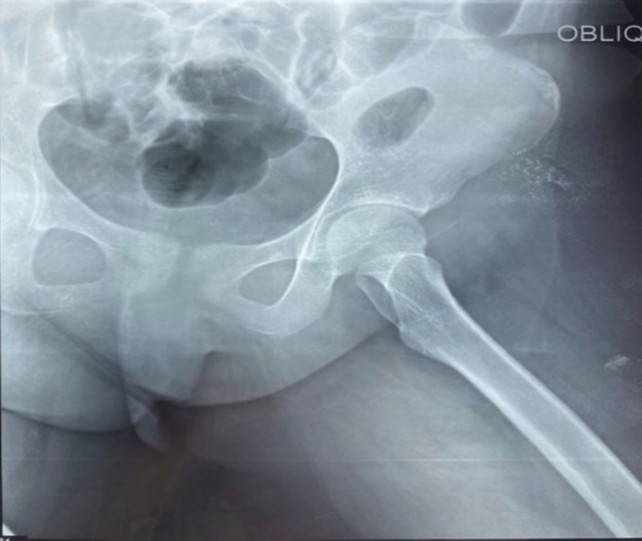

The initial laboratory findings: white blood cells (WBC) were 13.6×109/L (neutrophils: 11.83×109/L, lymphocyte count: 1.22×109/L), hemoglobin: 9 g/dL, normal glycated hemoglobin (HbA1c): 5.4%, platelet count: 81 ×109/L, erythrocyte sedimentation rate (ESR): 80 mm/hour and C-reactive protein (CRP): 12 mg/dL. Serum urea and creatinine were increased to 62 mg/dL and 1.8 mg/dL, respectively. Thyroid Stimulating Hormone was increased (TSH) at 6.6 mIU/mL (range: 0.35-5.1), normal free T4: 1.19 ng/dL (range: 0.5-1.4), normal free T3: 3.42 pg/ml (range: 1.8-4.2). The electrolytes and liver function tests were within normal range. The urinalysis showed bacteria 1+, red blood cells (RBC) > 100/HPF, WBC 38/HPF. In addition, the X-Ray of the left hip showed no bone/joint abnormality (Figure 3), whereas the ultrasound indicated an intra-articular collection around 16 mm (Figure 4).

Figure 3: Intra-articular collection of left hip joint

Figure 4: X-ray of left hip joint